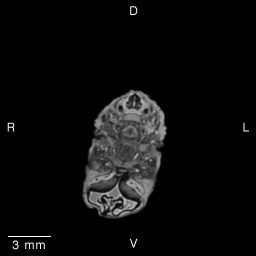

Stage 19 (Day 47), transverse slice 13